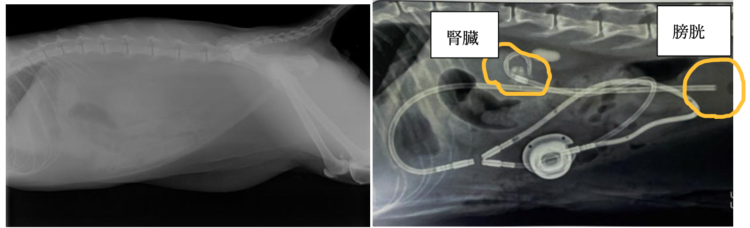

SUBシステムは、腎臓に設置するカテーテル(1)、膀胱に設置するカテーテル(2)、その2本のカテーテルを連結させるポートという金属の部品(3)で構成されます。

腎臓と膀胱に固定した2本のカテーテルをポートという金属の部品で連結させ、皮下で固定し、お腹を閉じて手術が終了となります。

上の写真は左が手術前の腹部のレントゲン画像です。SUBシステムを設置すると右の写真のように腎臓から膀胱への尿管の代わりとなる道ができます。手術後は、皮膚の上からポートに針を刺せるので、ポートを介して採尿や洗浄が行えます。